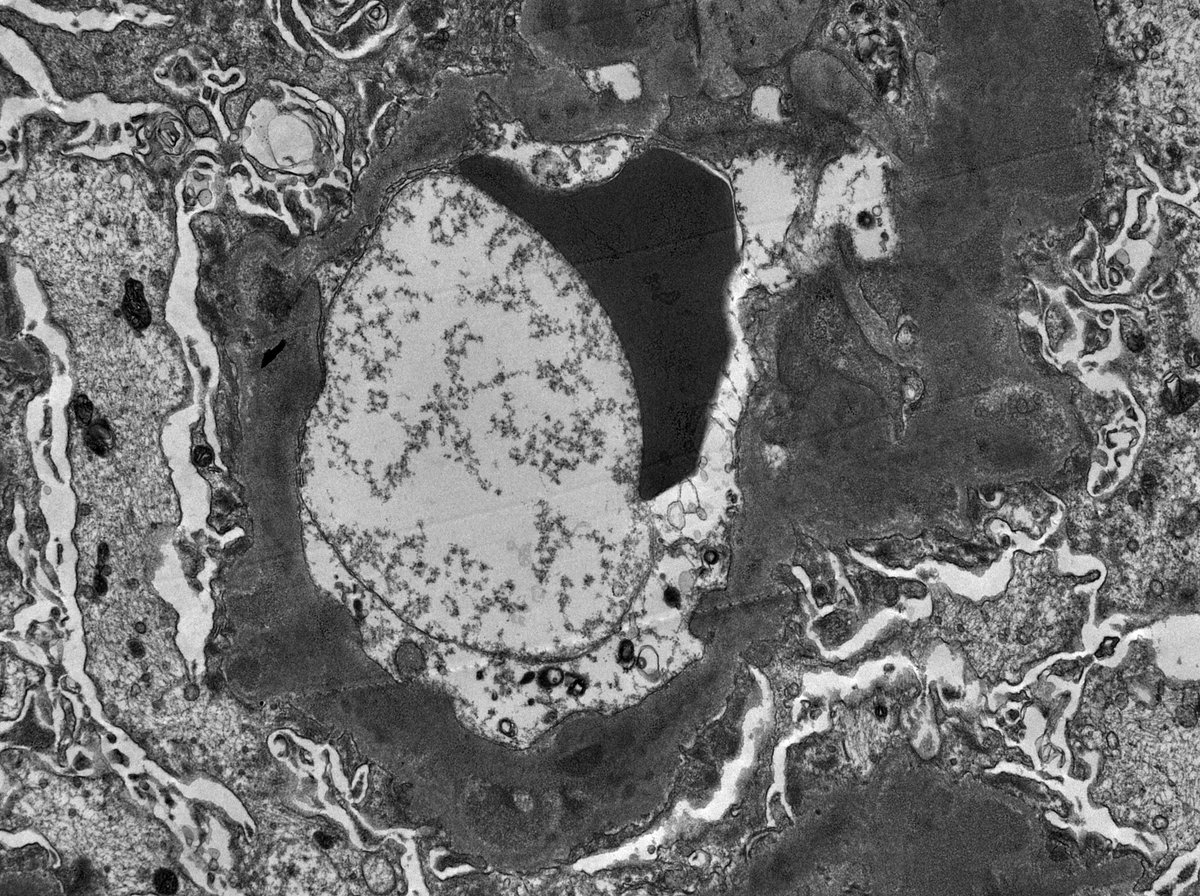

C3 GN in 11 yo boy with proteinuria, hypertension, low C3 (normal C4). EM shows irregular thickening of glomerular capillary wall and mesangial expansion by electron dense deposits. The deposits are somewhat ill-defined with early sign of resorption.